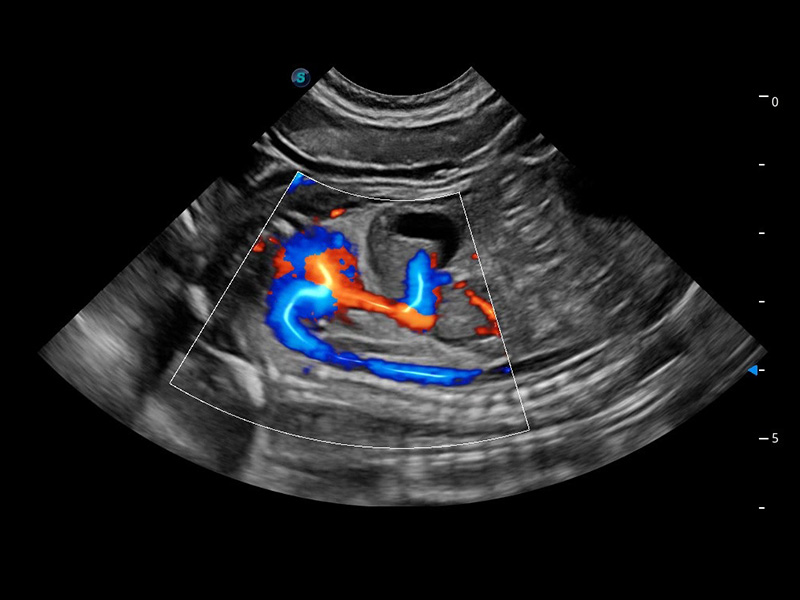

ProPet 60 作為一款高端臺式動物超聲設備,為動物醫(yī)生的日常診斷提供了一系列貼合動物臨床需求、解決臨床實際問題的高級成像功能。憑借全系列高清探頭,滿足醫(yī)生對腹部、心臟、生殖、淺表、肌骨等成像的所有需求,切實幫助您提升檢查效率,提高診斷信心。

動物是人類最親密的朋友和最值得信賴的伙伴。開立醫(yī)療也一直致力于探索動物專用的超聲影像解決方案。 全新推出的ProPet系列,是開立在動物超聲影像智能化、專業(yè)化、精準化的一次跨越式革新。動物不能用言語來表述自己的不適,通過超聲影像,ProPet系列搭建了動物醫(yī)生與不同物種溝通的“橋梁”,為動物醫(yī)生注入了“治愈之力”。